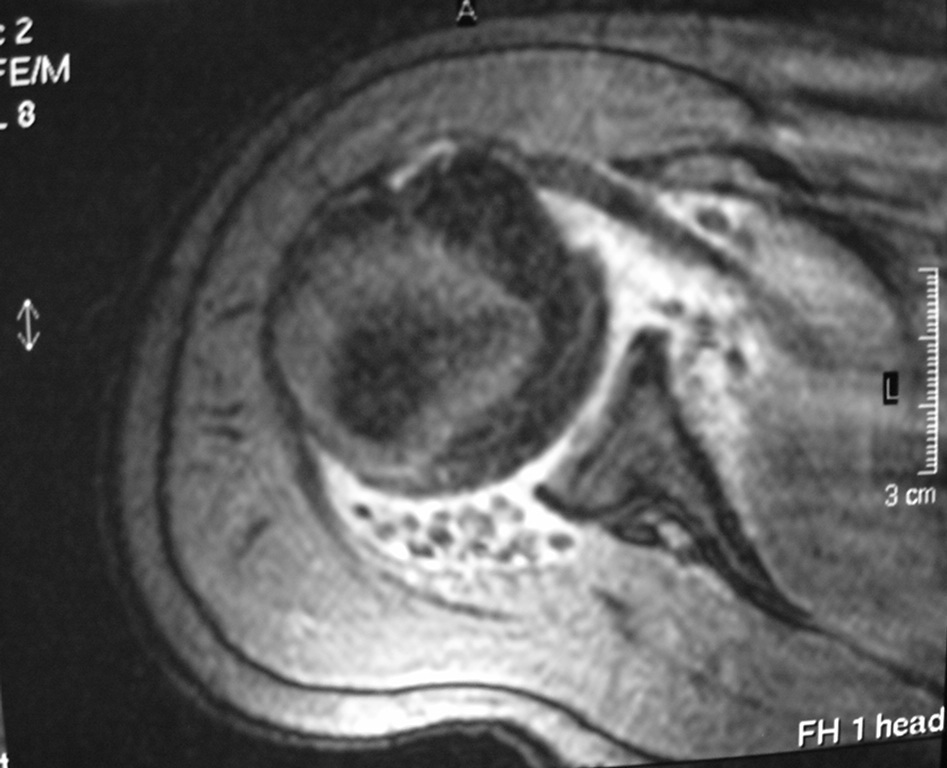

Synovial chondromatosis is an uncommon, benign, process that occurs in large joints, such as the knee (50%), hip, elbow, or shoulder. This process mainly affects synovium and hence most commonly arises from joints and tendons which are lined by synovium. Synovial Chondromatosis may also affect bursae and extend into surrounding soft tissues. This condition is seen in patients between 20 and 50 years of age and most commonly in men (male-female ratio of 2-4/1). The patient usually complains of pain, stiffness, crepitance, swelling, and joint locking. The knee is the most common site to be affected. Symptoms are long-standing and progressive. The plain x-ray may be normal (5 to 33%) or there may be small flecks of calcification (Fig. 1 & 2). On MRI the nodules of cartilage are easily seen. MR imaging may also show synovial thickening, joint erosions and intraarticular calcifications. The signal characteristics of these intraarticular bodies depend of their composition. If mineralization is not present the signal intensity follows the cartilage signal with intermediate signal on T1 images and high signal on T2 weighted MR images. Uniformly calcified bodies follows bone density on all sequences with bone marrow signal centrally and low signal peripherally (Fig. 3-5). Histologically the cartilage is arranged in nodules, which are quite cellular (Fig. 7-9). Synovial lining is present surrounding the cartilage nodules (Fig. 8). The cartilage nodules are often referred to as loose bodies however they are not really loose and embedded in the synovium lining. This is considered a metaplastic condition as opposed to a true neoplastic condition. Rarely it may turn into a malignancy usually a low grade chondrosarcoma. Malignant change is suggested by deep erosions into adjacent bone.

Fig. 4 & 5. MR images of the right shoulder. Axial (Fig. 4) and coronal (Fig. 5) T2-weighted images demonstrate high signal in the right shoulder corresponding with proliferation and swelling of the synovium. Multiple bodies with low signal that follow bone density in all sequences.